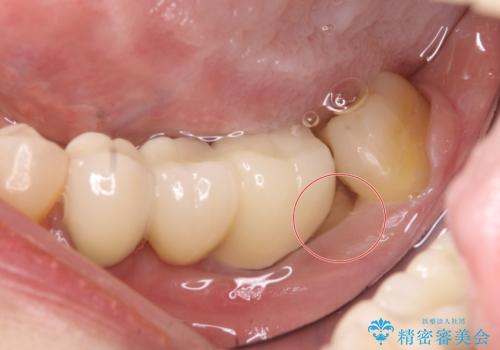

- 左下のブリッジの適合が悪く、虫歯になっていました。

左下6を抜いてからブリッジを入れるまでに放置してしまったために、左下7が前に倒れたこと、左下8も後ろから押す向きに生えていたこともあり、左下7がかぶせものを入れづらい状態になっていたためと考えられました。

また左下7は倒れていたため、清掃性が悪く近心のポケットは7mmありました。

そのため、左下8を抜いて、左下7を部分矯正で後ろに起こしてからブリッジを新製することとしました。